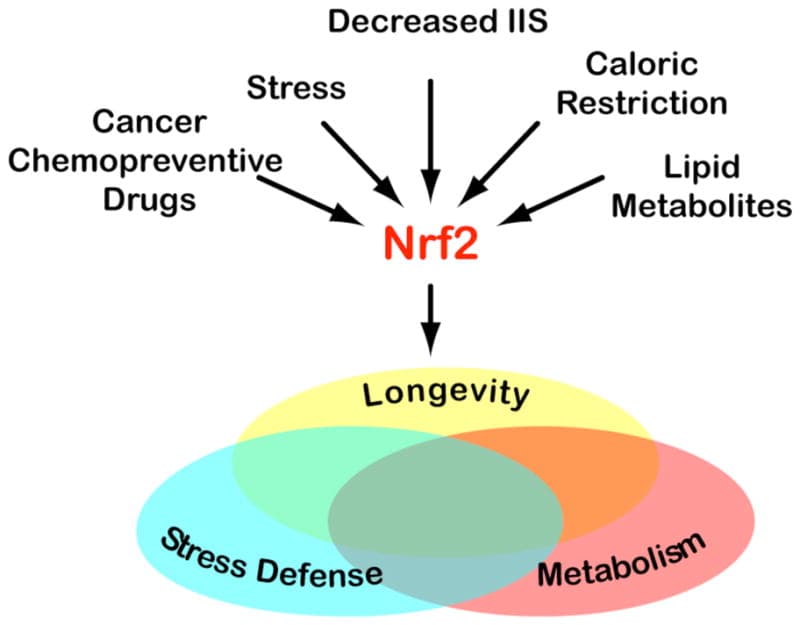

Melatonin combats "molecular terrorism" at the mitochondrial level by cleaning up (scavenging) ROS (reactive oxygen species) and RNS (reactive nitrogen species). ROS and RNS can damage DNA and proteins, so melatonin scavenges them while creating new protective molecules. R

It also activates NRF2. R

Melatonin initiates molecular cleanup in the blood stream. R

It induces the expression of γ-GCS (γ-glutamylcysteine synthetase), the rate-limiting enzyme of glutathione synthesis, which protects cells against oxidative stress and regulates cell proliferation. R

13. Increases Longevity

In fruit flies, mice and rats, melatonin increased longevity. R